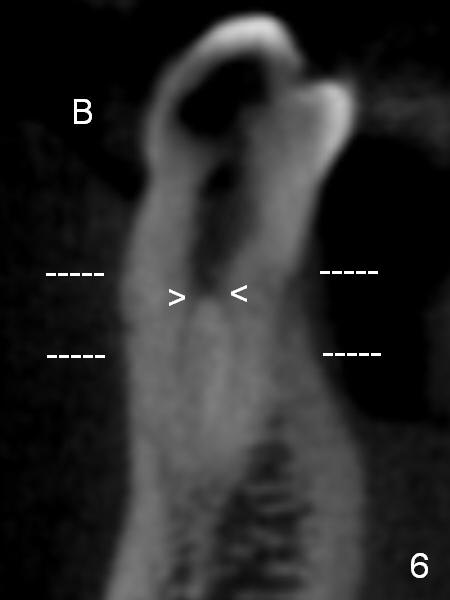

In fact CBCT has ben taken for #14 RCT and is reviewed prior to this case. If CT were reviewed, finding the extra canal would be easier (Fig.6 coronal section). It appears that the apical canals are blocked (Fig.7). The canal is split at the middle of the root, as shown in Fig.8,8' (axial upper section, as shown by the upper dashed line in Fig.6) and in Fig.9,9' (axial lower section, as shown by the lower dashed line in Fig.6). The buccal canal should not have been debrided with 40/.04 rotary file (30/.04 would have been better). In all, the tooth has two fused roots (Fig.3,9,9').